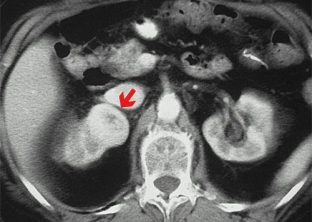

- computed and magnetic resonance imaging help to clarify the structural features of ovarian tumors;